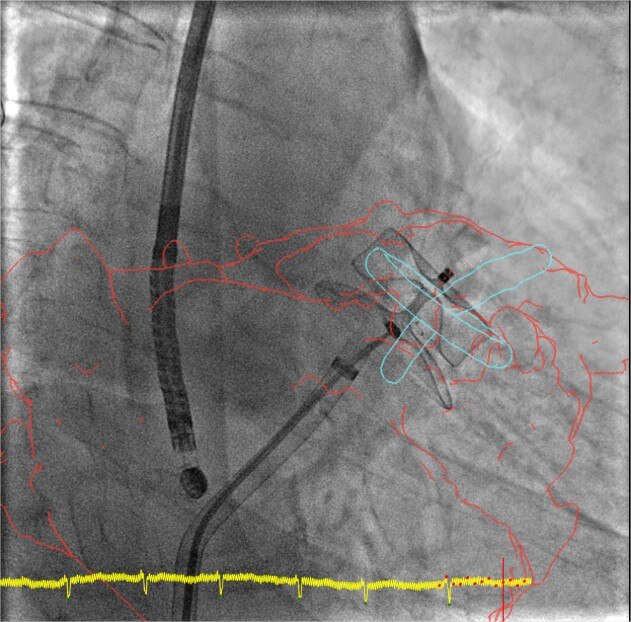

product-product-categories-Intervantional - 2016-valve_22.jpgGuida

La fusione 3D aiuta a guidare ogni passaggio con sicurezza, dalla puntura trans-settale all'impiego del dispositivo. Riduzione significativa del tempo della procedura, diminuendo contemporaneamente mezzi di contrasto e dose.